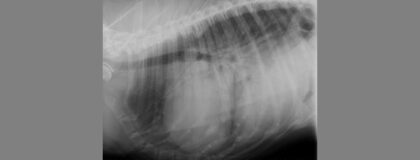

Die Dilatative Kardiomyopathie (DCM) stellt eine der wichtigsten erworbenen Herzerkrankungen, insbesondere beim großen Hund wie z.B. dem Neufundländer oder der Deutschen Dogge, dar. Kernproblem hierbei ist eine systolische Dysfunktion des linken Ventrikels, welche zu einem verminderten Cardiac output und einem kongestiven Linksherzversagen führen kann. Nicht jede systolische Dysfunktion des linken Ventrikels ist jedoch zwingend eine DCM. Wichtige Differentialdiagnosen sind z.B. hormonelle Störungen wie eine Hypothyreose, nutritive Störungen, Myokarditis oder Chemotherapieschäden. Eine genaue Aufarbeitung ist daher essentiell. Basis der Diagnostik und Einschätzung ist die Echokardiographie bei zahlreiche Messverfahren wie z.B. die Simpson Technik zum Einsatz kommen